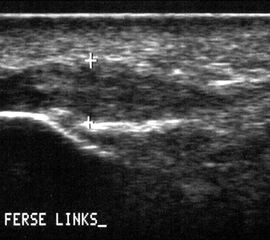

Die Sonographie zeigt im Falle einer Plantarfasziitis eine Verdickung der Plantarfaszie 24. Sie tritt etwas verzögert nach stattgehabter Überlastung und dem Schmerzbeginn auf und ist in ihrem Ausmaß ein guter Indikator für die Schwere der Erkrankung und die zu erwartende Behandlungsdauer. Die Rückbildung der Verdickung benötigt auch nach erreichter Schmerzfreiheit Wochen bis Monate.

In Abhängigkeit des gesamten klinischen Bildes und der Vorgeschichte kann ein MRT z.B. zum Ausschluss einer Stressfraktur oder Ruptur der Plantarfaszie erforderlich werden. Es hat sich bewährt, in Fällen eines mehrmonatigen Krankheitsverlaufes und sonographisch verdickter Plantarfaszie >8mm (Normwert <4mm) vor Therapiebeginn ein MRT zum Ausschluss von Teilrupturen durchzuführen. Obwohl auch in diesen Fällen eine Stoßwellentherapie erfolgen kann, ist eine derartige Information aus juristischen Gründen von Bedeutung.

Die sonographische Diagnostik eignet sich primär zur Erkennung schmerzhafter Prozesse im Verlauf der Achillessehne und kann bei Bedarf durch Röntgen bzw. MRT ergänzt werden. Besonders bei längeren Verläufen und kräftigen spindelförmigen Schwellungen (>9mm, Normwert <5mm) im Bereich der kritischen Zone sollte ein MRT zum Ausschluss von Nekrosezonen und Partialrupturen vor Therapiebeginn veranlasst werden. Die sonographisch leicht zu erfassende Veränderung der Sehnendicke im mittleren Sehnenanteil ist ein guter Indikator für die Schwere der Erkrankung und die Beurteilung des Behandlungsverlaufes. Die sichtbaren Veränderungen am distalen knöchernen Ansatz der Sehne sind diskreter.